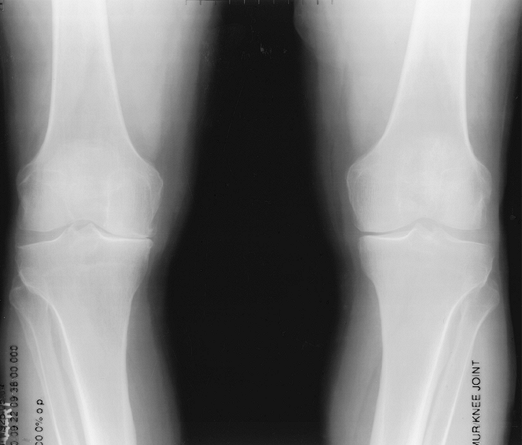

|

FIGURE 5-51 Patellar views of both knees showing lateral tilt without subluxation because of lateral pressure syndrome.